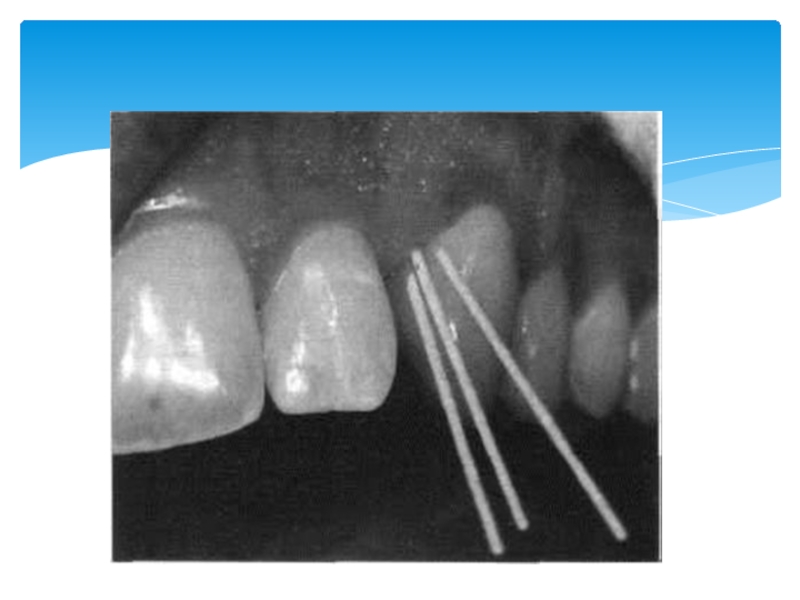

Слайд 22Определение насыщенности тканей аскорбиновой кислотой. А - внутрикожная проба; Б - языковая

проба

Насыщение тканей аскорбиновой кислотой уменьшает проницаемость капилляров, стимулирует функциональную деятельность органов и тканей, оказывает положительное влияние на обмен коллагена и др.. Для определения тканевой насыщенности витамином С на слизистую оболочку спинки языка инъекционной иглой наносят каплю индикатора (0,06% раствор натриевой соли 2,6-дихлорфенолиндофенола), который восстанавливается аскорбиновой кислотой при комнатной температуре, - индикатор обесцвечивается.